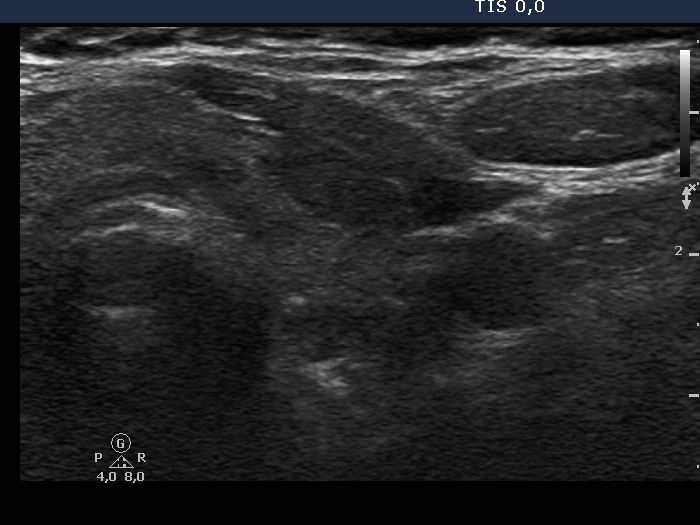

Examination in 2013 (first row of images):

Clinical data. A 50-year-old woman was referred for evaluation of a nodular goiter. The patient has been treated for hypothyroidism for 16 years.

Palpation: Both lobes were a bit firm, no nodule was palpable.

Laboratory test: TSH 4.01 mIU/L on daily 100 microgram levothyroxine.

Ultrasonography. The thyroid was minimally/moderately hypoechoic and had several discrete minimally/moderately hypoechoic lesions.

Cytology was performed from the lesion in the central part of the right lobe and resulted in Hashimoto's thyroiditis.